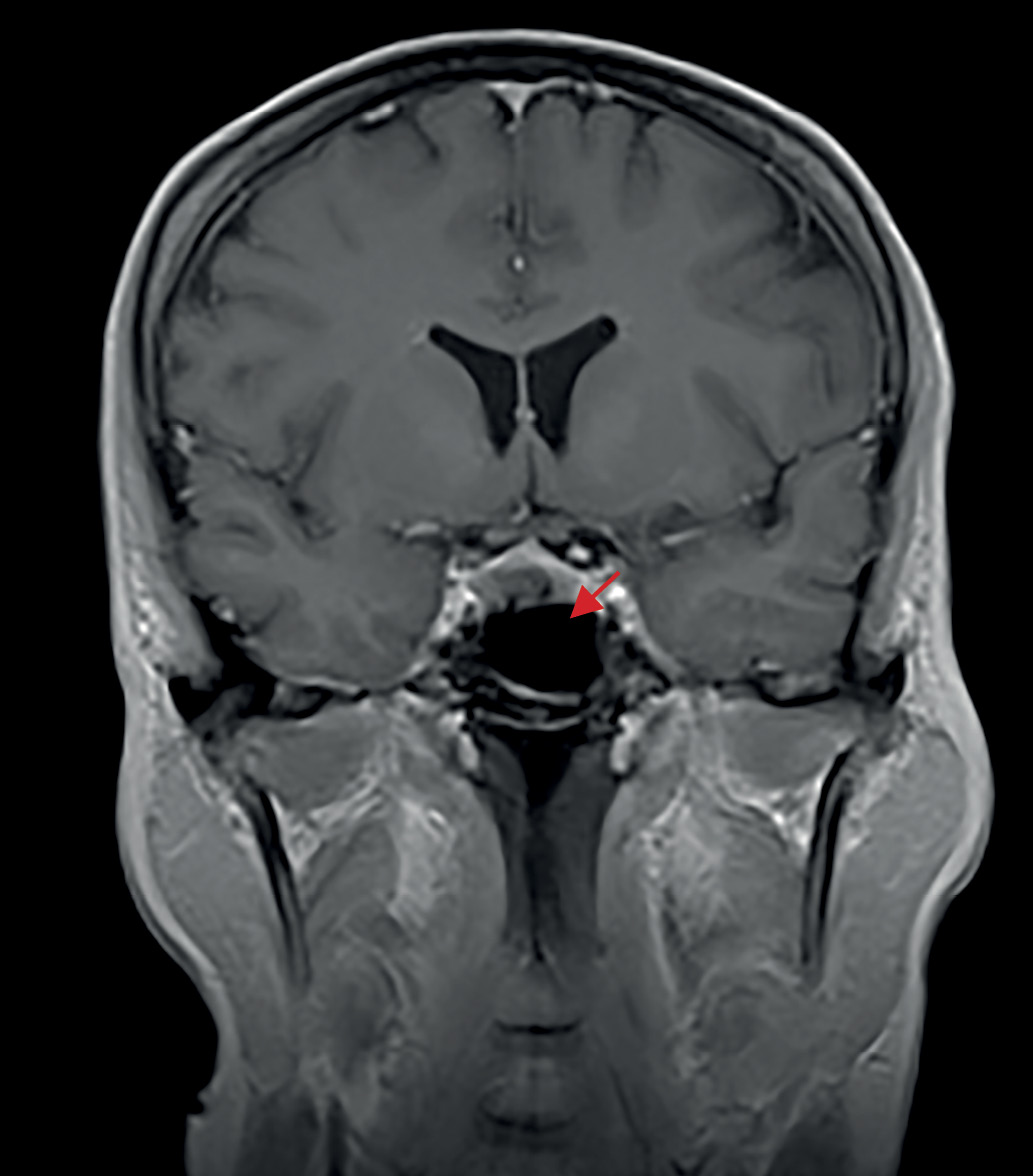

В июне 2020 г., на фоне сильного эмоционального стресса, повторно возникли жалобы на изменение внешности по типу «лунообразного лица», значительное повышение аппетита, увеличение массы тела на 8 кг за 6 мес без изменения диеты, выраженную слабость. По данным лабораторных исследований — рецидив гиперкортицизма: кортизол слюны, собранной в 23.00, — 69 (0,5–9,65) нмоль/л, кортизол в суточной моче — 2433,0 (100–379) нмоль/сут, АКТГ в сыворотке крови утром 166 (2–25,5) пг/мл, кортизол — 712 (64–327) нмоль/л. По данным МРТ головного мозга от июля 2020 г. (рис. 2) послеоперационные изменения селлярной области, без динамики по сравнению с 2018 г. Специфического лечения назначено не было, была направлена на консультацию в ФГБУ «НМИЦ эндокринологии» Минздрава России, где в сентябре 2020 г. при обследовании наблюдался регресс лабораторных признаков гиперкортицизма: выявлено незначительное повышение кортизола слюны, собранной в 23.00, — 10,28 ммоль/л (норма до 9, 65 нмоль/л), кортизол в суточной моче — в пределах референсных значений, результат малой дексаметазоновой пробы положительный — кортизол 45,0 нмоль/л. Данных за наличие нарушения углеводного обмена получено не было (глюкоза сыворотки крови — 4,68 ммоль/л). По результату рентгеновской денситометрии — без существенных изменений. Также наблюдались исчезновение внешних проявлений эндогенного гиперкортицизма и отсутствие характерных для данного заболевания жалоб. Несмотря на отсутствие полной лабораторной ремиссии, в связи с компенсацией клинической картины повторное хирургическое лечение показано не было, рекомендовано динамическое наблюдение.

Рисунок 2. МРТ головного мозга после трансназальной аденомэктомии, 2020 г.

2. Рисунок 2. МРТ головного мозга после трансназальной аденомэктомии, 2020 г.